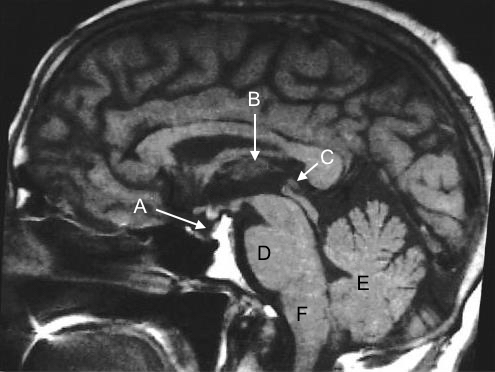

A 4-year-old child is brought to the clinic complaining of headaches that have developed over the last month and are most intense when lying down. He has also been experiencing nonbloody, nonbilious emesis for the past two weeks, which usually happens early in the morning. Furthermore, the youngster experiences periodic fuzzy vision, especially while gazing up at the mirror when brushing his teeth. Bilateral papilledema, difficulty to glance upwards, and bilateral eyelid retraction are all seen on physical examination. Sodium, growth hormone, luteinizing hormone (LH) , and follicle-stimulating hormone (FSH) testing is routine. Given the emesis and papilledema in the early morning, a brain tumor is suspected, and an MRI is requested. Which of the following is the most likely site of the patient's brain lesion?

A) A

B) B

C) C

D) D

E) E

F) F